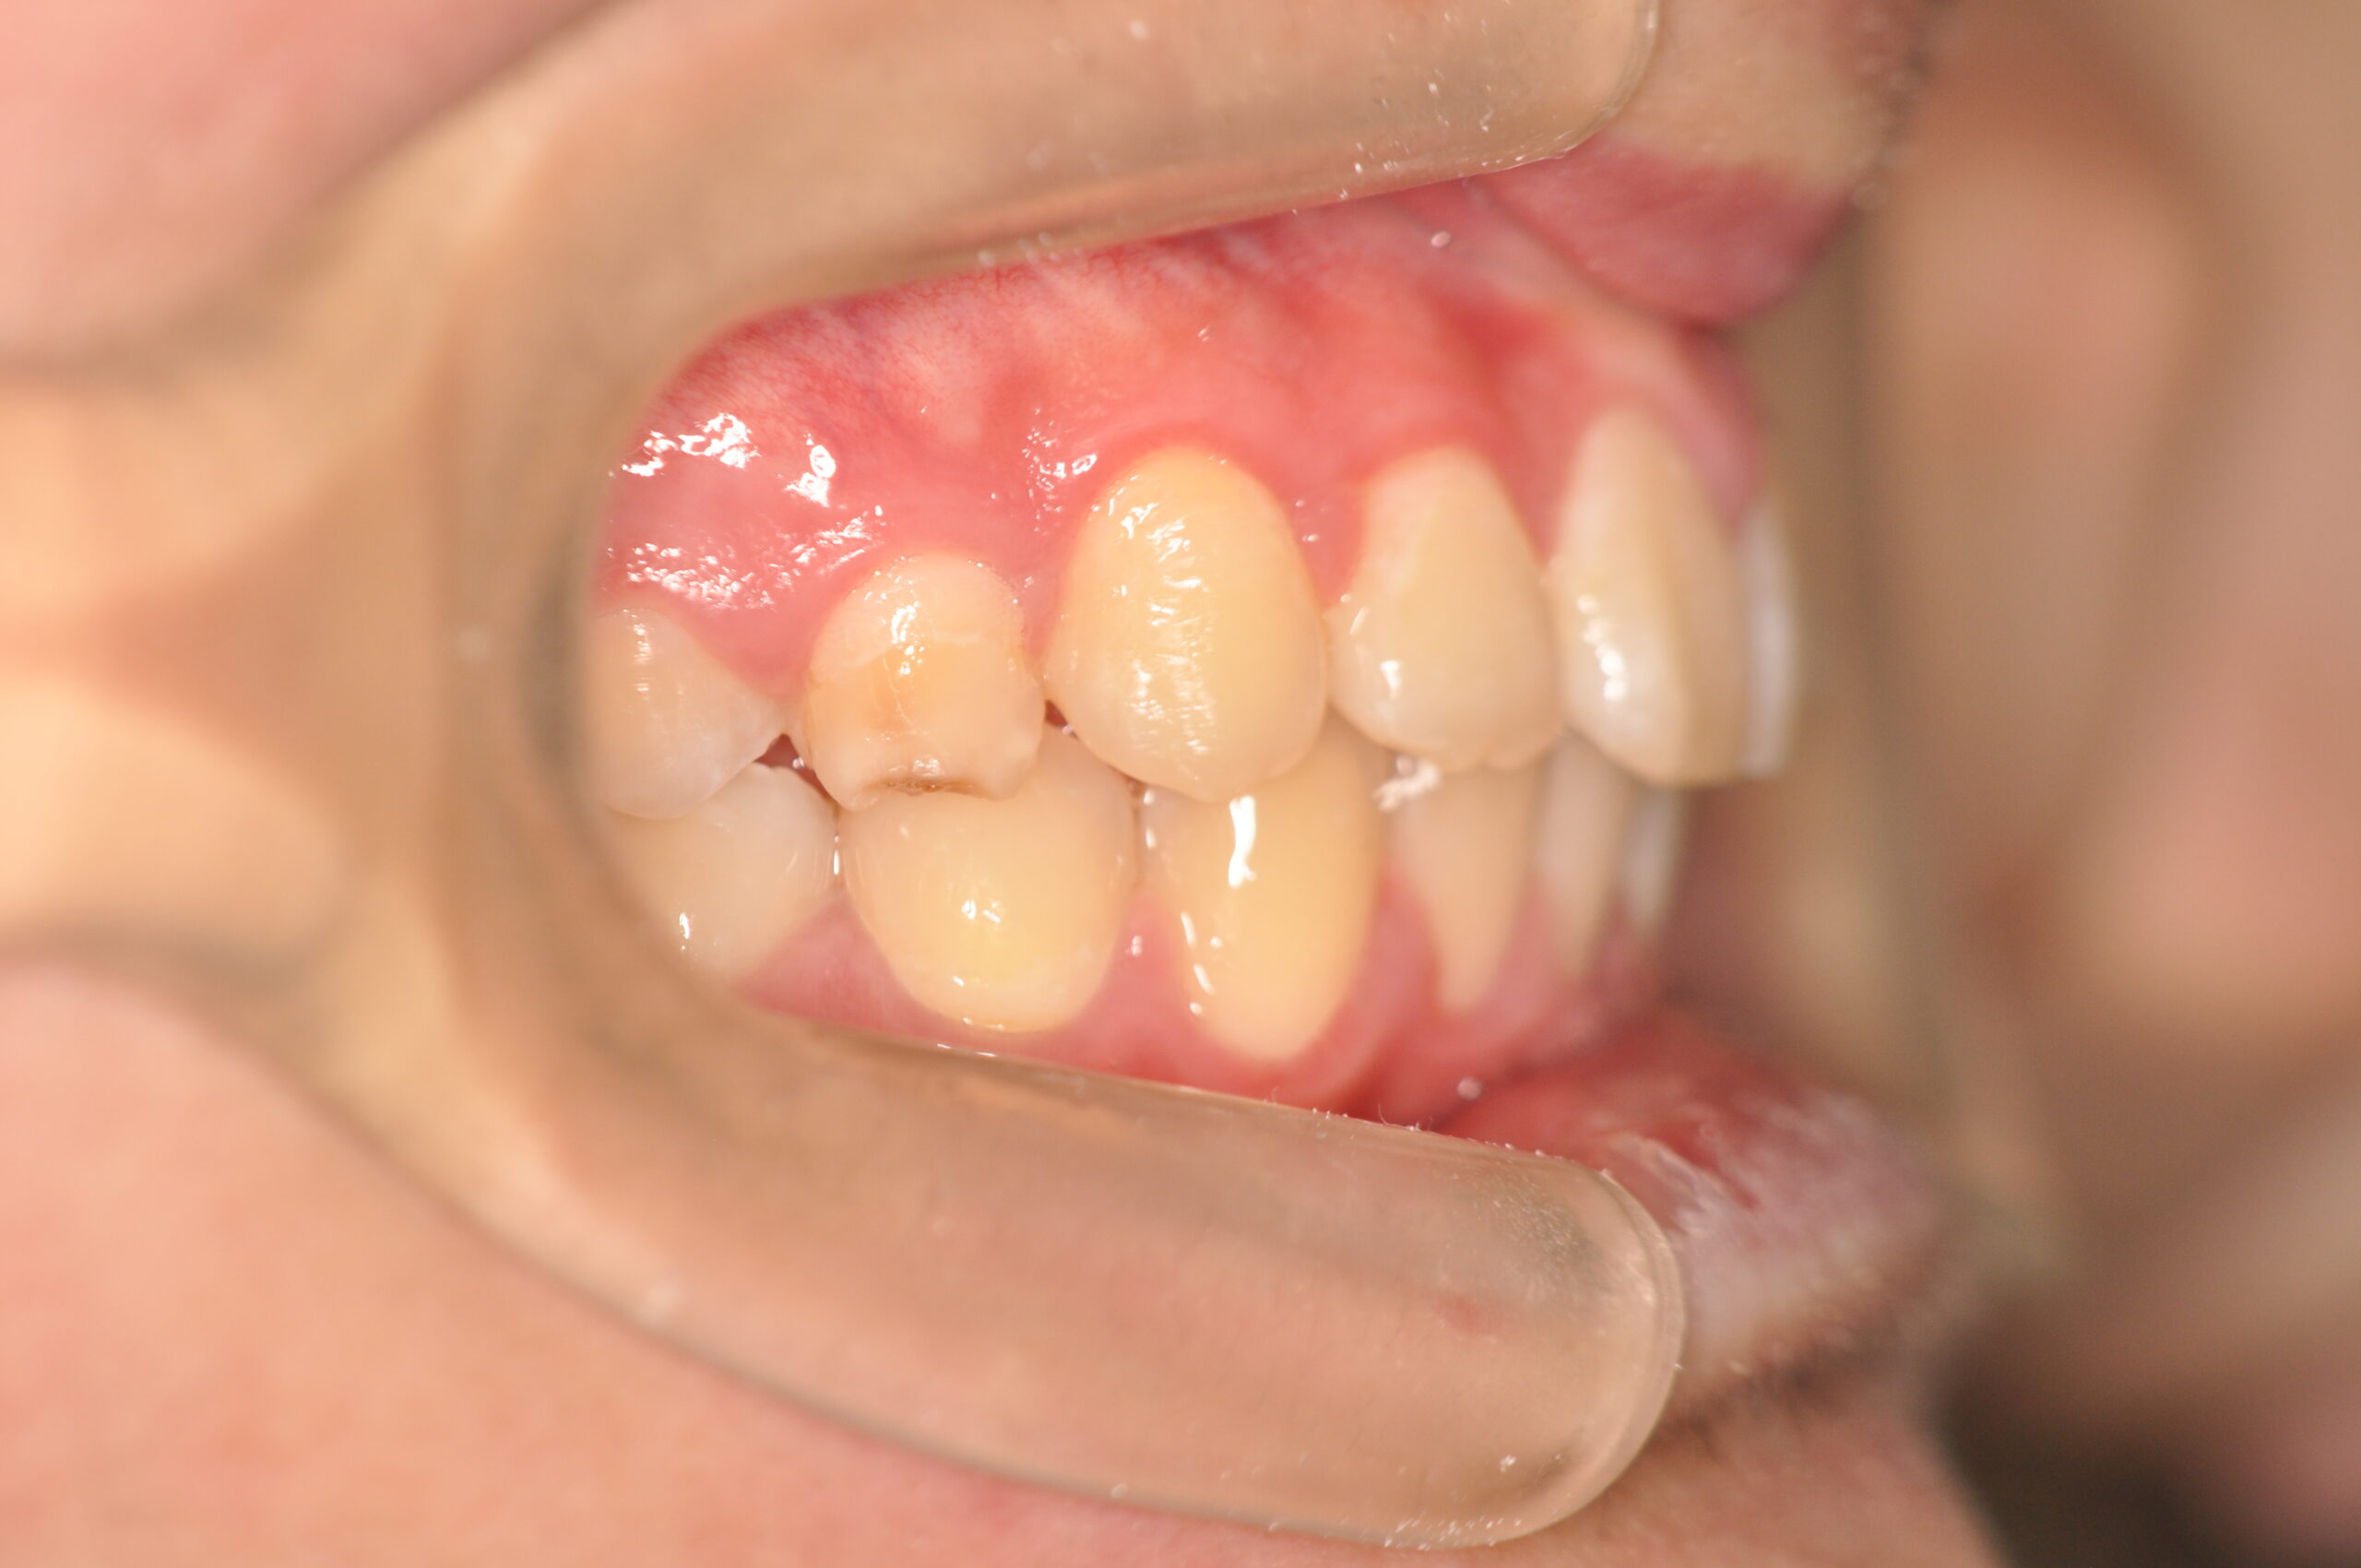

16歳 | 性 別 | 男性 |

| 治療期間 | 1年6ヶ月 | 費 用 | 矯正施術料:850,000円 調整料:4,000円/月 |

| 治療内容の詳細 | 初診時16歳の男性で、歯のがたつき、かみ合わせを気にされ来院しました。 検査の結果、アングルⅡ級2類不正咬合と診断しました。 治療としては、非抜歯の上、セルフライゲーションブラケット装置(デーモンシステム)で配列を行いました。 同時に顎間ゴムにて咬合関係の改善を行いました。 治療期間は、1年6ヶ月でした。 |